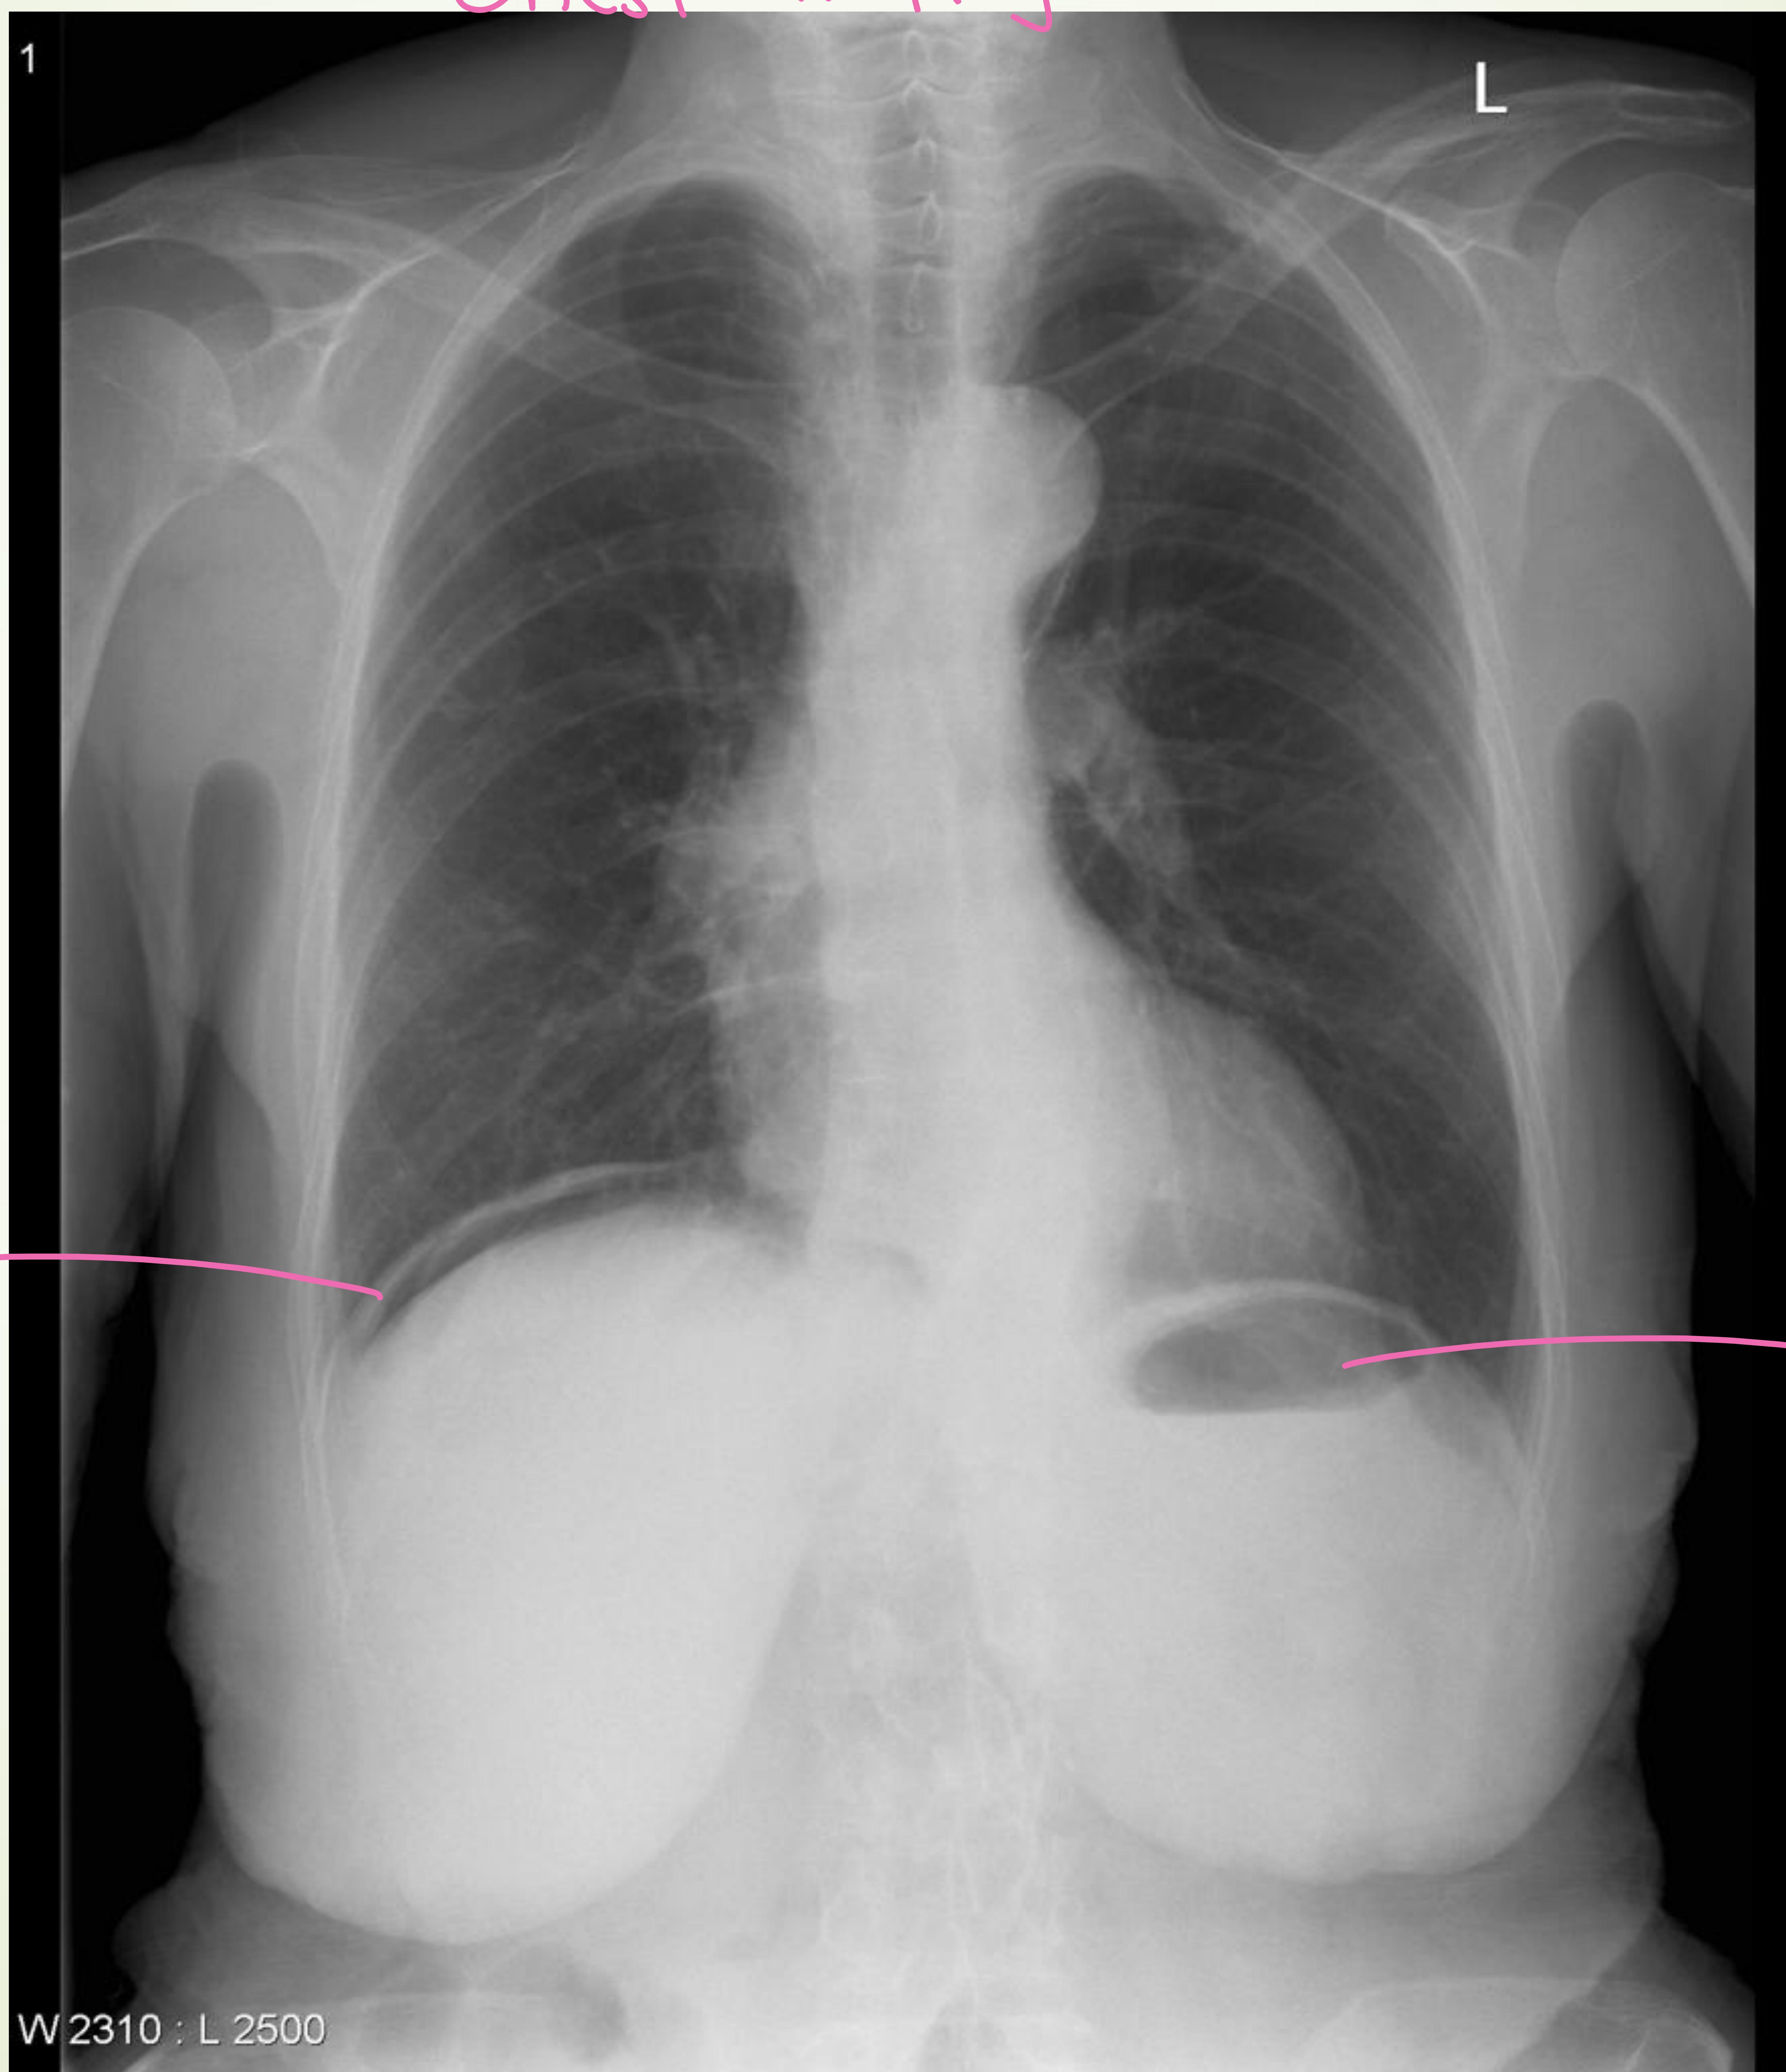

Chest X-Ray showing air under the diaphragm.

- Imaging: upright abdominal + chest X‑ray (look for free air, though its absence does not exclude perforation); consider CT abdomen/pelvis with contrast if stable

- Recognition: abrupt severe epigastric pain followed by signs of peritonitis

- Investigations: CBC, LFTs, lipase, emergent abdominal X‑ray series (free air may be absent)